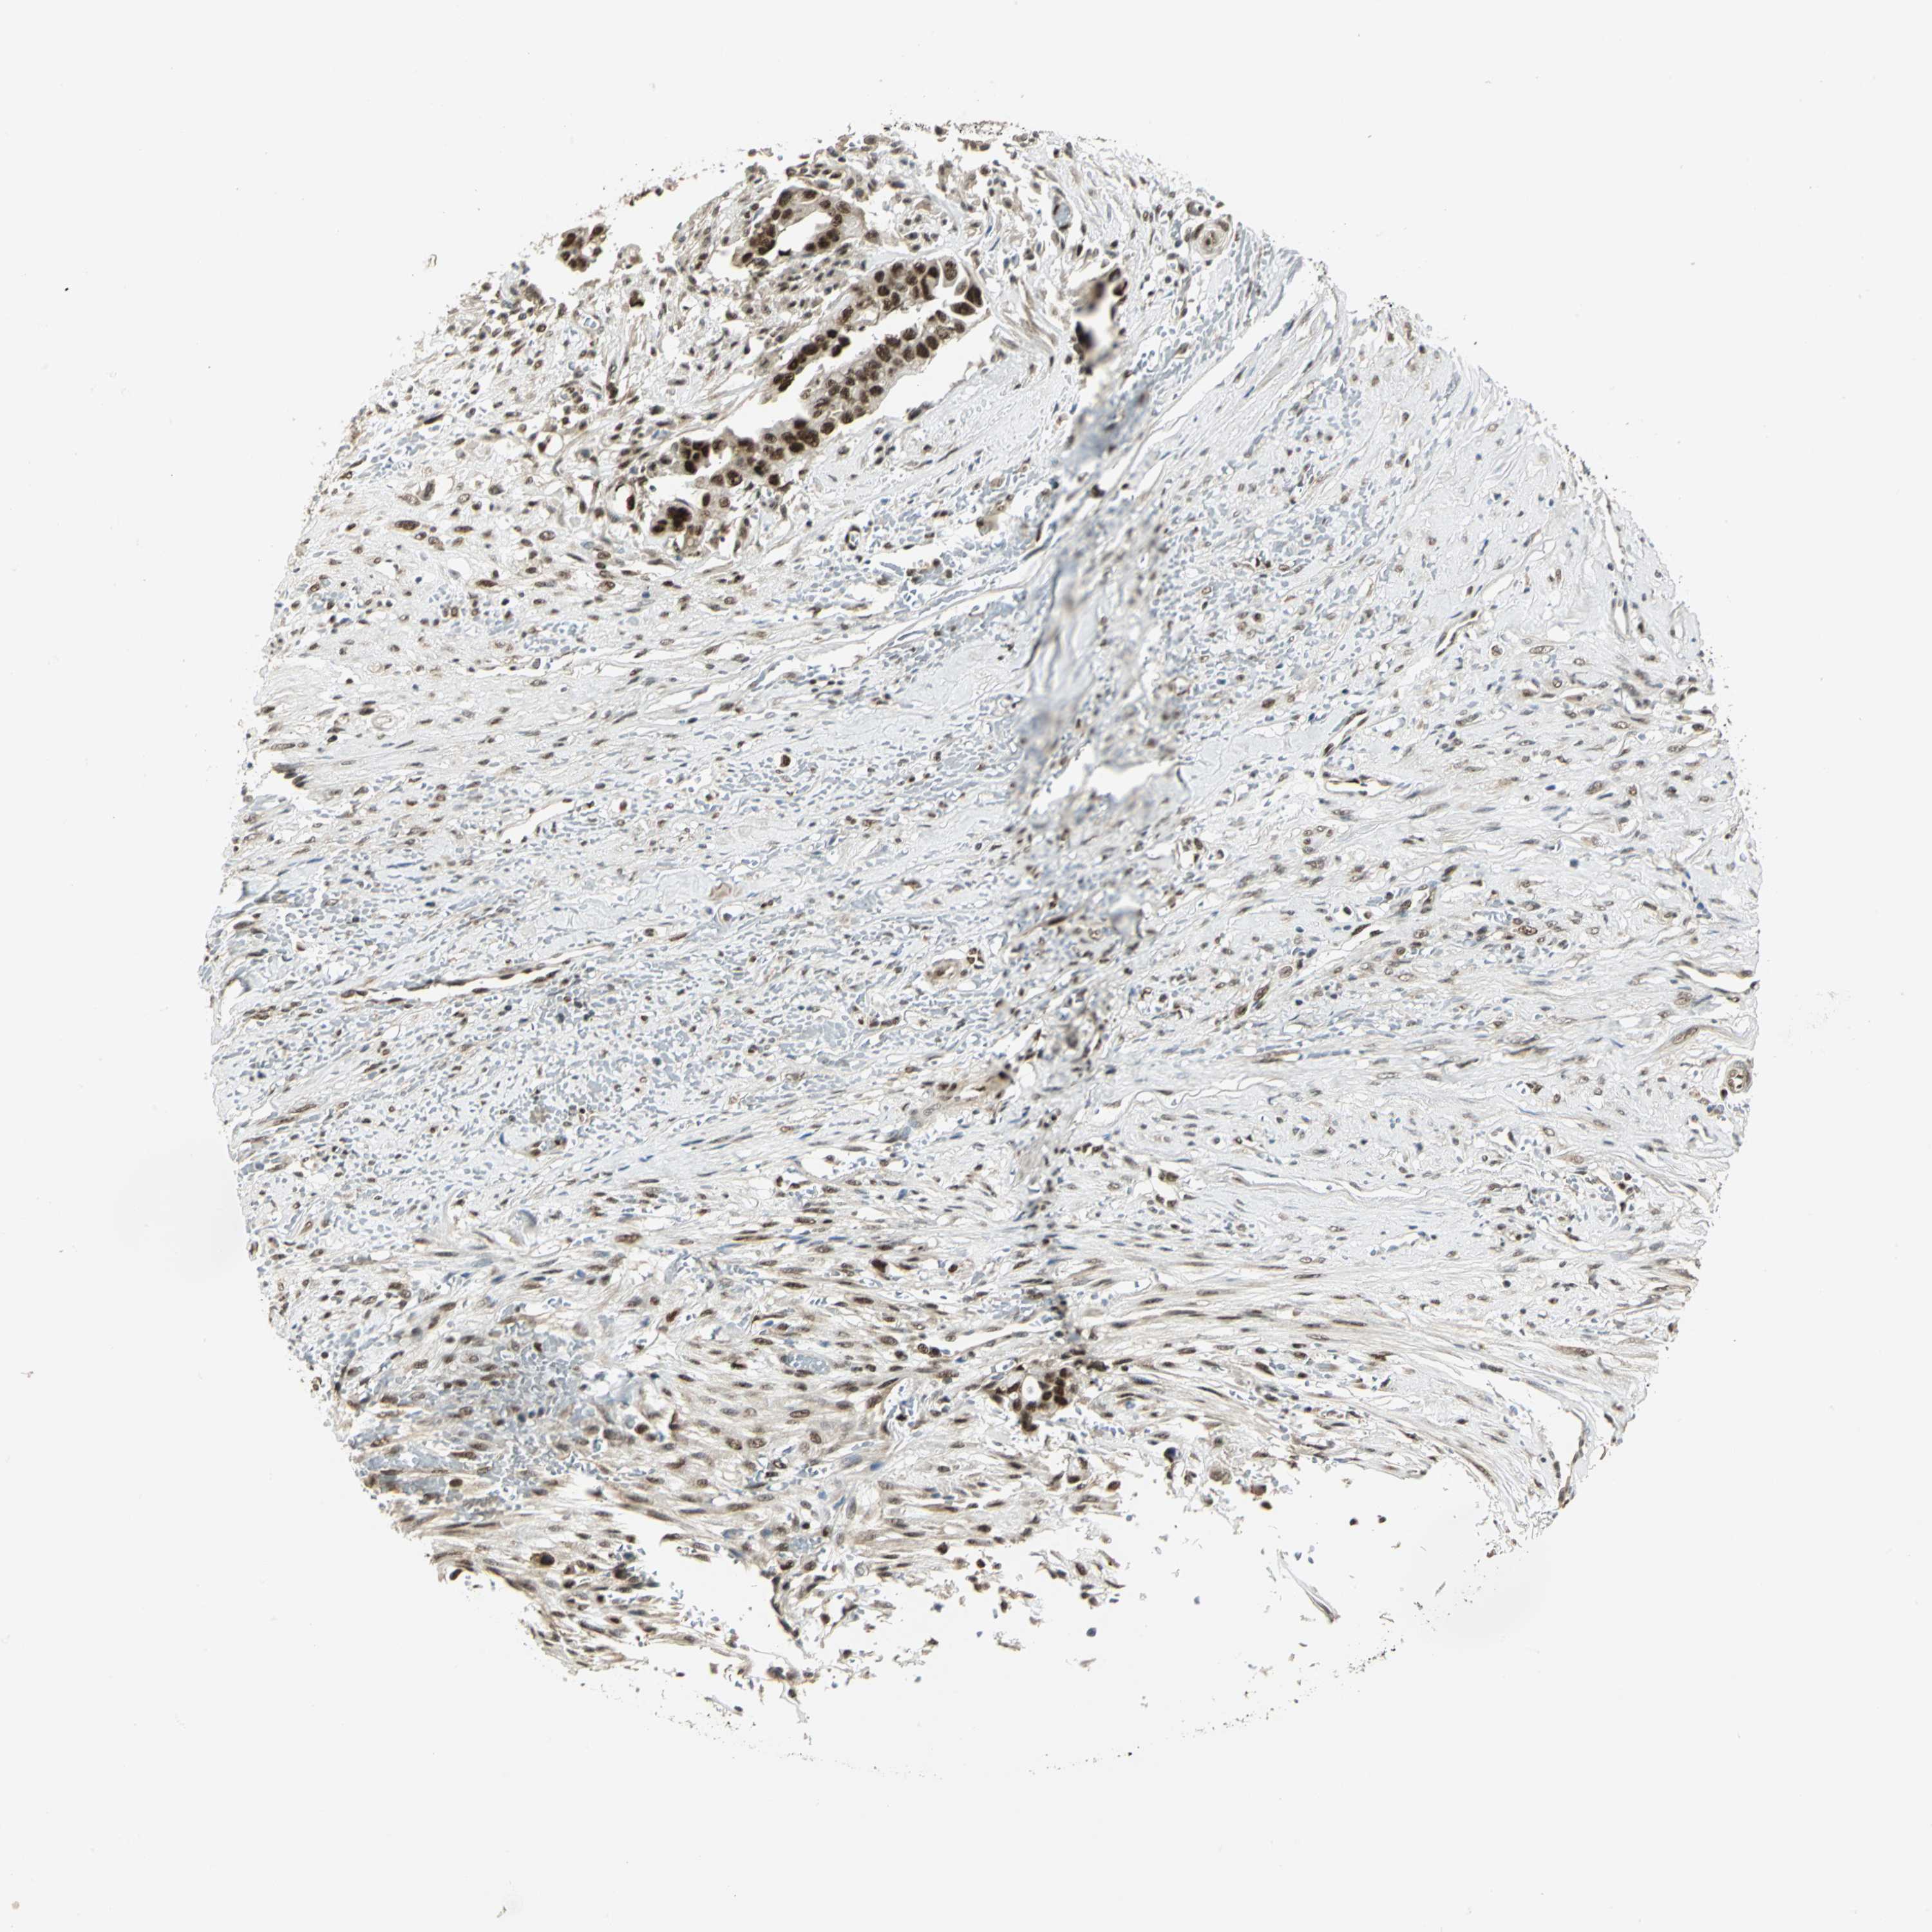

LIVER CANCER - Protein expressioni

A mouse-over function shows sample information and annotation data. Click on an image to view it in a full screen mode. Samples can be filtered based on level of antibody staining by selecting one or several of the following categories: high, medium, low and not detected. The assay and annotation is described here.

Note that samples used for immunohistochemistry by the Human Protein Atlas do not correspond to samples in the TCGA dataset.

Antibody stainingi

Antibody staining in the annotated cell types in the current human tissue is reported as not detected, low, medium, or high, based on conventional immunohistochemistry profiling in selected tissues. This score is based on the combination of the staining intensity and fraction of stained cells.

Each image is clickable and will lead to virtual microscopy that enables deeper exploration of all samples and also displays staining intensity scores, fraction scores and subcellular localization as well as patient and tissue information for each sample.

Antibody HPA020043

Antibody CAB005868

Staining

High

Medium

Low

Not detected

Intensity

Strong

Moderate

Weak

Negative

Quantity

>75%

75%-25%

<25%

None

Location

Nuclear

Cytoplasmic/membranous

Cytoplasmic/membranous,nuclear

Carcinoma, Hepatocellular, NOS

Cholangiocarcinoma